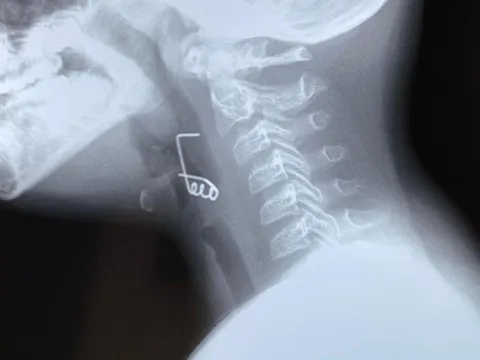

TP.HCM: Bé trai 9 tuổi nuốt lò xo vào cổ họng

Bé M. nhập viện trong tình trạng nuốt đau, vướng nhiều. Khai thác bệnh sử, cha của bé cho biết bé M. bị tự kỷ. Trong lúc chơi, anh phát hiện bé hóc dị vật nên chuyển đến Bệnh viện Tai mũi họng cấp cứu.